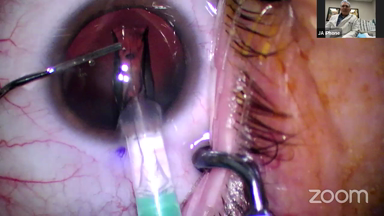

Viewer Discretion Advised: The videos may contain graphic images of surgical procedures that could be disturbing. Viewer discretion is advised. The site is intended for users who are 18 years or older, and no viewers under 18 years of age are allowed unless the use of the site is part of a class within an institution of secondary education and the viewing is supervised by an adult education professional.